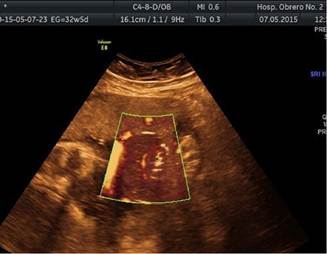

Acudió a control médico portando ecografía del tercer trimestre, que informaba: embarazo de 31 semanas, feto con una malformación en miembro inferior izquierdo que afecta tercio inferior de pierna, tobillo y pie (Edema vs Tumoración). Se practica segunda ecografía, esta vez, detallada en la Unidad de Medicina Fetal del Hospital Obrero N° 2 de la Caja Nacional de Salud - Cochabamba, que informó de un embarazo de 32 semanas con presencia de anillo constrictor en la unión de las 2/3 partes superiores de la pierna con el 1/3 distal, con edema distal importante (Figura 1), la vascularización distal conservada al momento del examen (Figura 2), concluyendo como: Síndrome de Brida amniótica con anillo constrictor en 1/3 inferior de pierna izquierda. La unidad de Medicina fetal recomendó mantener conducta expectante debido a la presencia de vascularización distal al anillo.